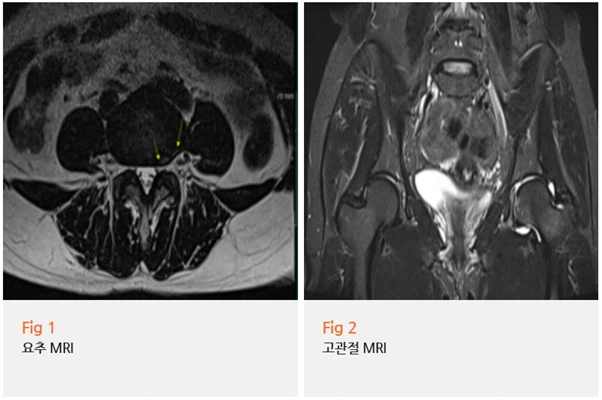

그래서 먼저 당일 요추와 고관절 MRI 검사를 진행했어요.

결과를 보니, 네……

요추 4-5번 추간판 질환이 함께 있었고,

좌측 고관절 부위에서 염증 소견이 확인됐어요.

네, 최종 진단은 고관절 충돌 증후군이었습니다.